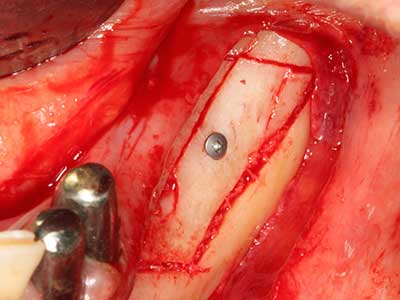

Пиезохирургията има допълнителни предимства при събиране на костни блокове. В допълнение към високата прецизност при остеотомията, описана по-горе, употребата на фините режещи накрайници значително намаляват загубата на материал. Голяма загуба на материал по време на събиране може да се очаква с дебелите накрайници, особено при употреба на борери Линдеман (Lakshmiganthan, Gokulanathan et al. 2012). Базалното разделяне, което е необходимо, особено за присадка на блок при ретромолар, е улеснено от специално създадени правоъгълни триони. В резултат на това, пиезохирургията е разглеждана като прецизна, улеснена и безопасна процедура за събиране на костни блокове в ретромоларното пространство (Happe 2007) (Фиг. 1-12).

Костната тъкан е не само минерализирана структура, тя съдържа и съществено количество колагенови влакна. Това означава, че тя има не само добра компресивна сила, но и известна степен на гъвкавост, която може да се възприеме като предимство при извършване на костна аугментация. В класическата процедура по разширяване чрез костно разделяне, атрофиралият алвеоларен гребен е разделен надлъжно и внимателно разширен след достигане на подходящата остеотомна дълбочина (Фиг. 13-16), в идеалния случай без допълнително отстраняване на периостеума (Brugnami, Caiazzo et al. 2014, Stricker, Fleiner et al. 2014). Системите с винт и пластини с увеличаване на разстоянието при разширяване са доказали ефективността си при разделяне на двете костни ламели, оставайки под прага на фрактурите. В общи линии, оставащата ширина на костта от поне 3–4 mm е задължителна (Chiapasco, Zaniboni et al. 2006), за да се гарантира добра гъвкавост и достатъчно костно покритие за бъдещото поставяне на импланти. Ако е необходимо, вертикалната остеотомия на едната или двете страни може да подобри гъвкавостта. Комбинацията с допълнителни техники за аугментация, особено в букалната страна, е описана като алтернатива на класическата техника.

Процедурата по разделяне е атравматична и няма голяма загуба на пространство, използвайки пиезотриони, и няма значителна разлика между импланти в разделени челюсти и импланти в алвеоларния гребен без костен дефицит (Chiapasco, Zaniboni et al. 2006, Danza, Guidi et al. 2009). Въпреки това, важно е да има достатъчно и продължително охлаждане, особено при ограничено и дълбоко разделяне, за да се избегне термичен стрес в апикално-остеотомните зони.